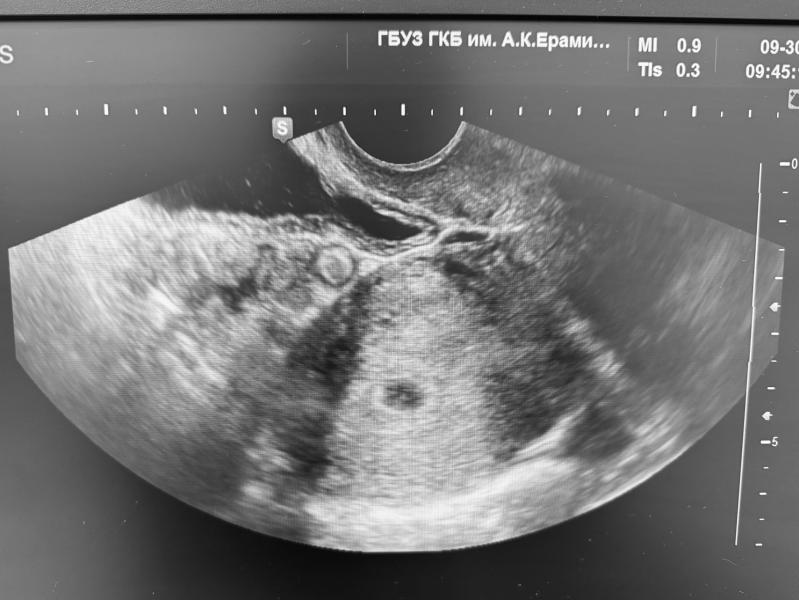

✔️ узи;

✔️ подтвердили, что беременность маточная;

✔️ выяснили, что плодное яйцо 3х недельного размера;

Очень рада, что удалось сделать узи, потому что являюсь обладательницей двурогой матки, а в интернете такое пишут … 🤣